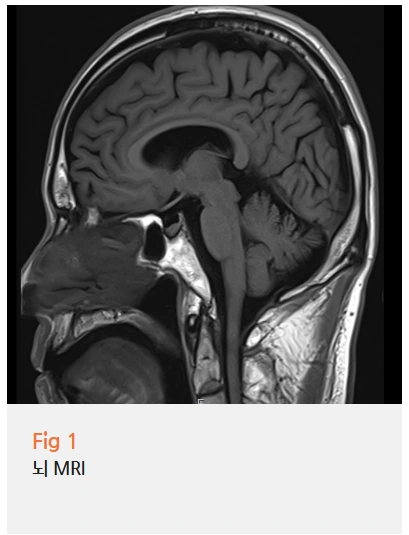

뇌 MRI도 찍어보고, 이비인후과도 가보고,

하지만 실제로 뇌 MRI를 찍어보면

대부분 특별한 이상이 없다는 결과가 나와요.

환자분께서 가져오신 뇌 MRI 결과를 확인해 봤어요.

다행히 뇌졸중이나 뇌출혈 같은 응급 상황은 아니었어요.

특별히 두통이나 어지러움을 유발할 만한 병변도 보이지 않았고요.